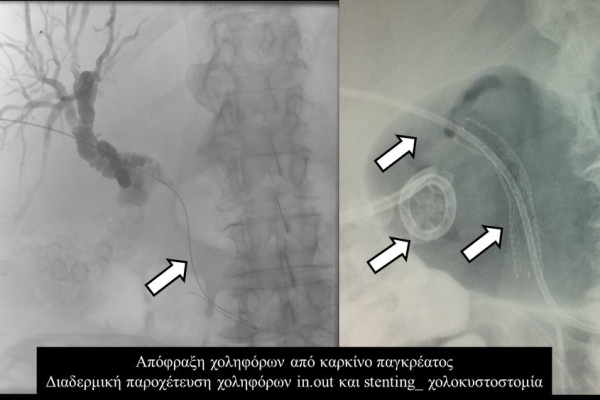

Η παροχέτευση των χοληφόρων σε αυτές τις περιπτώσεις θα πρέπει να γίνεται άμεσα, είτε ταυτόχρονα προς τα έξω και προς το 12κτυλο (έσω-έξω παροχέτευση), είτε μόνο προς τα έξω με τη βοήθεια pigtailκαθετήρα (εξωτερική παροχέτευση)

Σε περιπτώσεις όπου υπάρχει απόφραξη των χοληφόρων και ενδείκνυται η τοποθέτηση ενδοπρόθεσης (stent), τότε η βατότητα των χολαγγείων και η αντιμετώπιση του αποφρακτικού ικτέρου μπορεί να διασφαλιστεί με την τοποθέτηση ενδοπροθέσεων (stents).